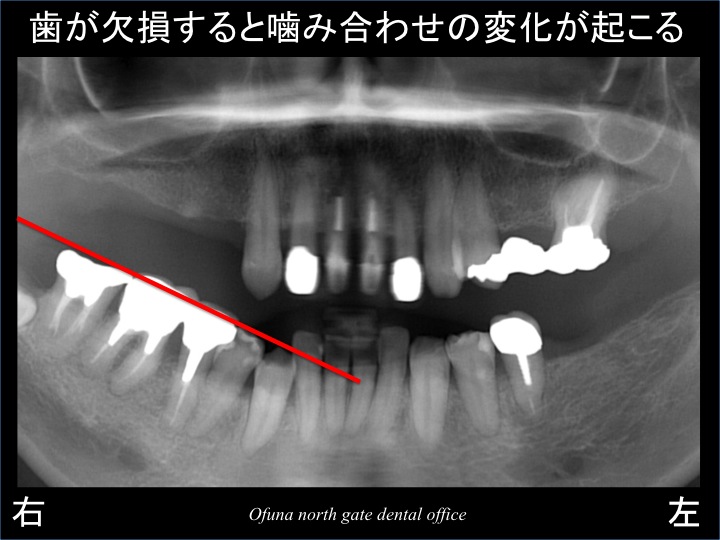

以下は初診時のレントゲン写真です。

この初診時のレントゲンから上顎右側の奥歯 と 下顎の左側の奥歯 が欠損しているのが分かるかと思います。

下顎の奥歯は、噛み合う歯がないめ 挺出(上方に動いた)しています。

挺出状態を分かりやすくするために線であらわしてみましょう!

下顎右側の奥歯の噛み合わせが斜めになっています。